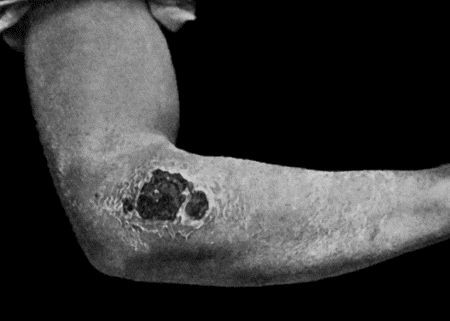

196 55.Recurrent Sarcoma of Sciatic Nerve

198 56.Sarcoma of Arm fungating